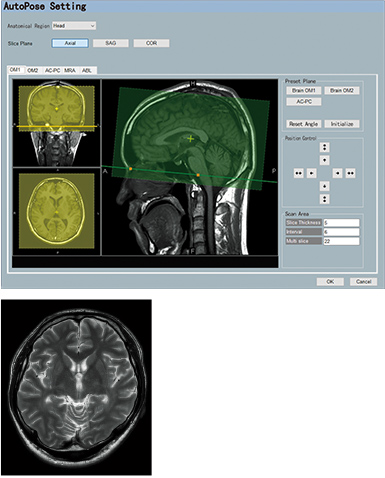

AutoPose is a slice line setting support function.

When the Scanogram imaging ends, the preset section is automatically set and can be registered up to five types of preset sections.

AutoExam enables setting of imaging conditions, positioning, image processing, image display, image storage, and image transfer functions to be carried out in one step during examination.

The operator can choose to perform semi-automated examinations and may stop, correct and restart imaging.